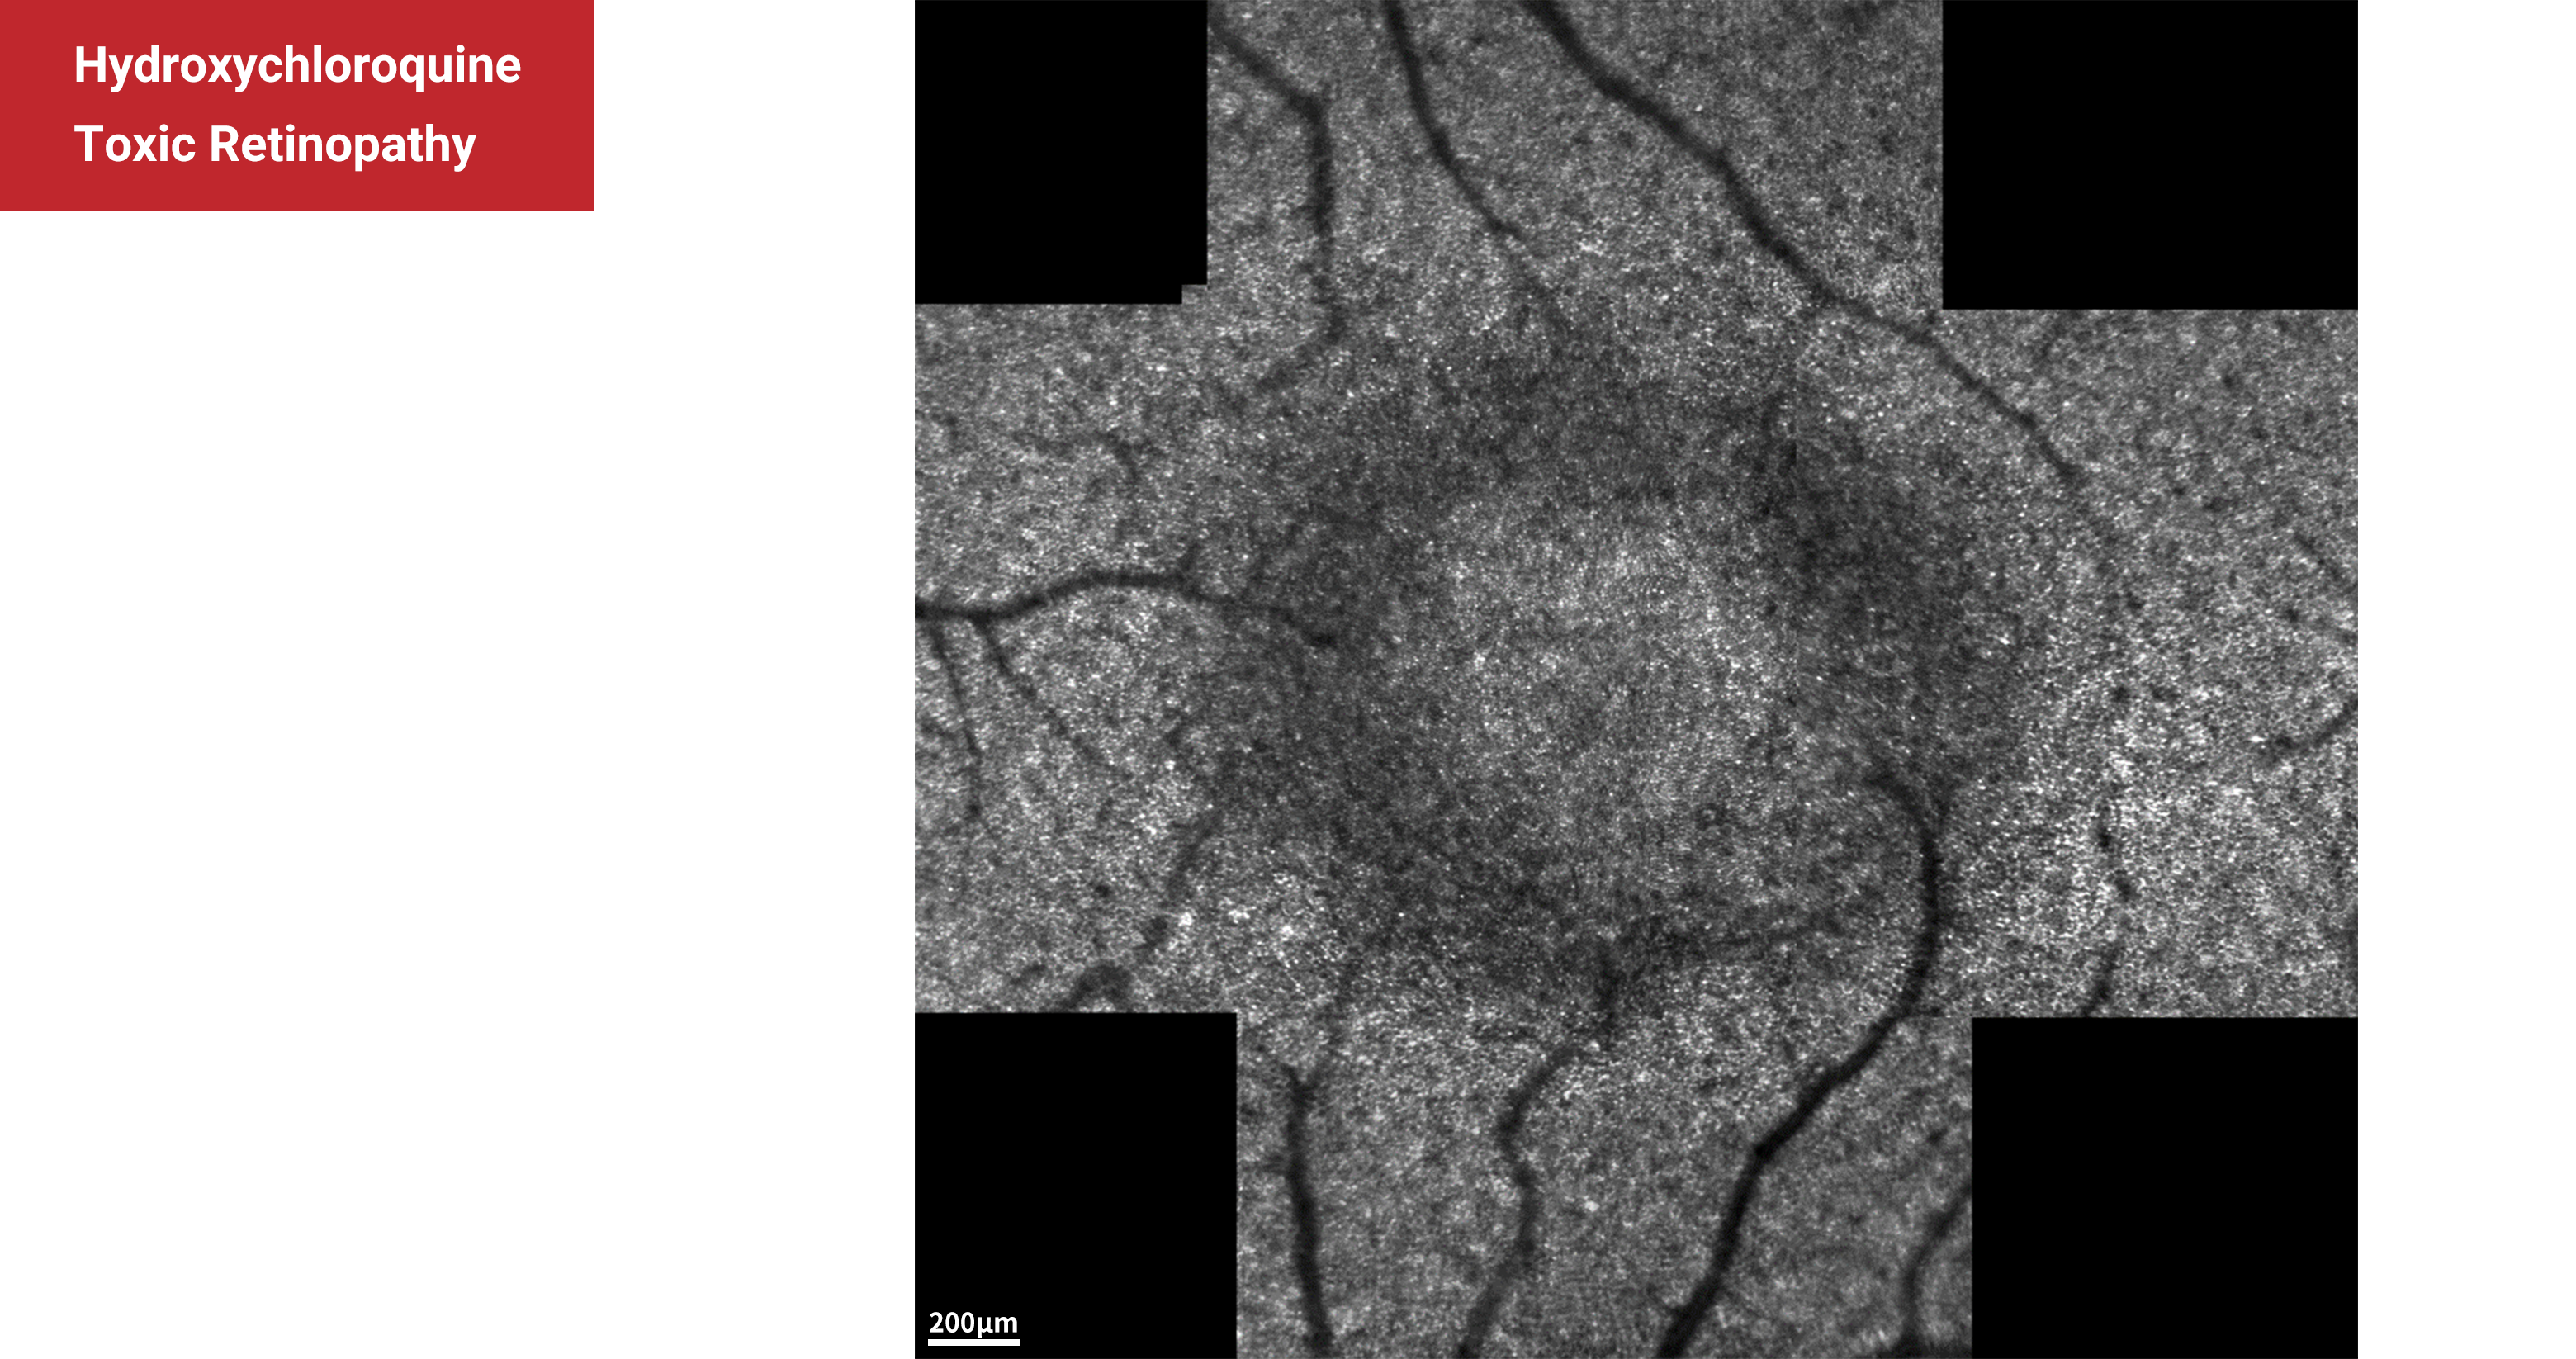

Hydroxychloroquine Toxic Retinopathy